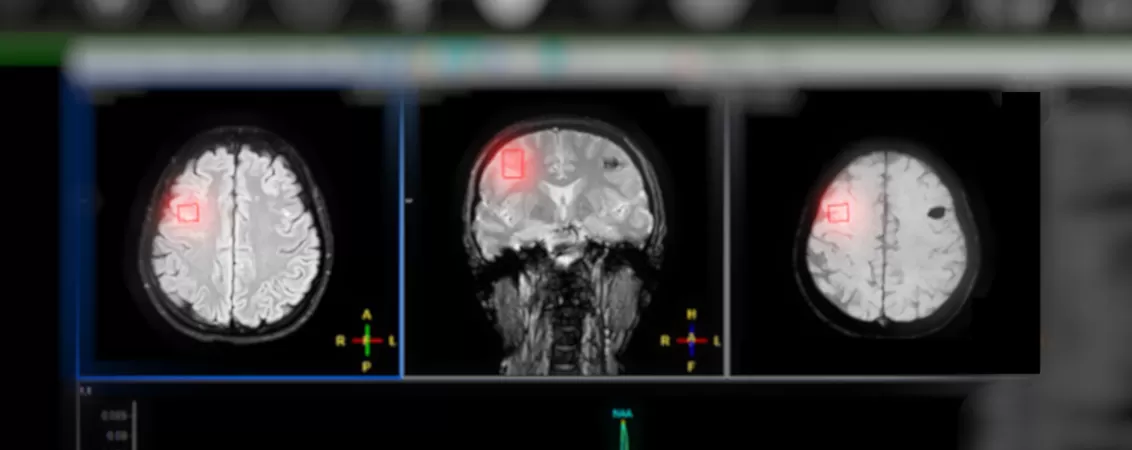

Spectroscopia este o tehnică prin care aparatul IRM măsoară modificările biochimice de la nivelul anumitor țesuturi (mai exact metaboliții din aceste structuri), aducând, de multe ori, informații adiționale ce ajută în stabilirea unui diagnostic cât mai precis și instituirii unui tratament specific.

Spectroscopia prin rezonanță magnetică nu este o investigație independentă, ci o secvență complementară a unei examinări IRM. Aceasta utilizează același aparat și același câmp magnetic ca și IRM-ul clasic, adăugând, practic, o dimensiune biochimică informației morfologice deja obținute.

IRM-ul standard oferă imagini detaliate ale structurilor anatomice, evidențiind modificări de formă, dimensiune sau semnal la nivelul țesuturilor. Spectroscopia completează aceste date cu informații despre ce se întâmplă la nivel molecular în interiorul acelor structuri.

Această complementaritate este esențială în practica clinică: există situații în care aspectul morfologic al unei leziuni pe IRM nu este suficient pentru a stabili diagnosticul cu certitudine. În astfel de cazuri, profilul metabolic furnizat de spectroscopie poate face diferența dintre un diagnostic corect și o eroare cu consecințe terapeutice importante.